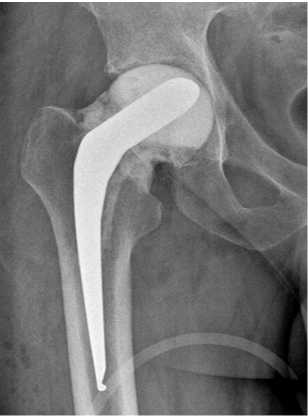

10.10.2023 произведена операция в объеме: удаление артикулирующего спейсера, тотальное бесце-ментное эндопротезирование правого тазобедренного сустава эндопротезом «ЭСИ» (рис. 7).

Рис. 7. Рентгенограмма правого тазобедренного сустава пациента К. в первые сутки после операции тотального бесцементного эндопротезирования правого тазобедренного сустава эндопротезом «ЭСИ»